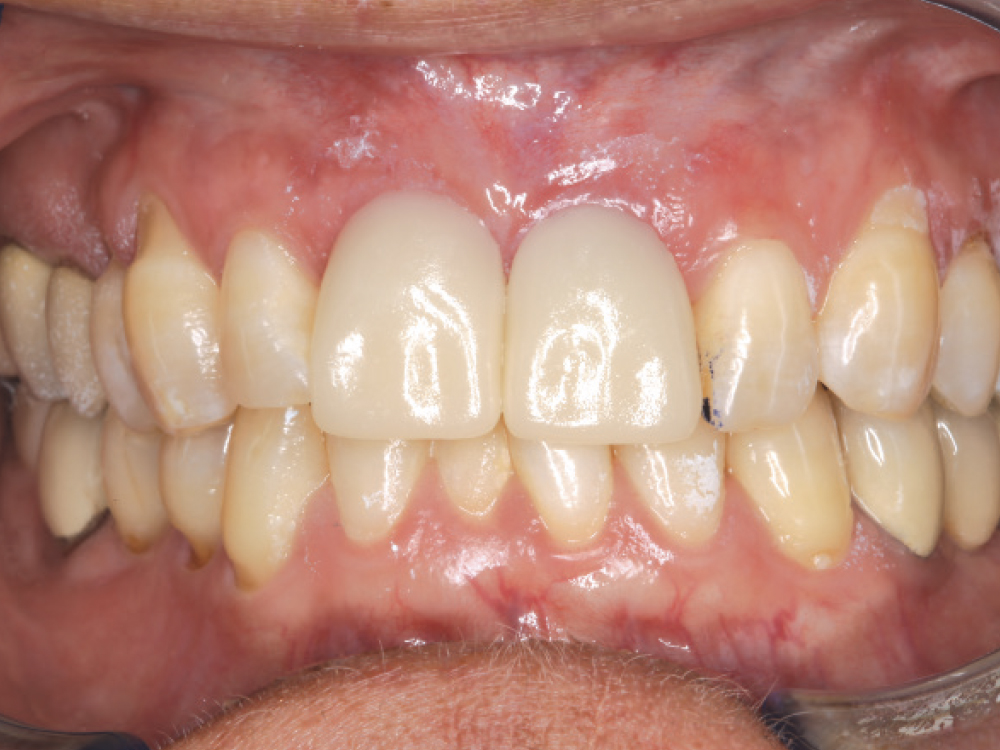

Gold-tone custom abutments

Life-like esthetic restorations

Scanner view of abutments

Four months after the surgical procedure, gold-tone custom abutments and all-ceramic crowns were delivered. The custom abutments and implant crowns were produced for a reduced fee because of the 20% discount offered by Glidewell for restorations over Hahn implants. The final restorations achieved esthetic, lifelike emergence profiles due to the soft-tissue management provided by the immediate provisional restorations during the healing phase. Note the crestal bone levels around the Hahn implants.